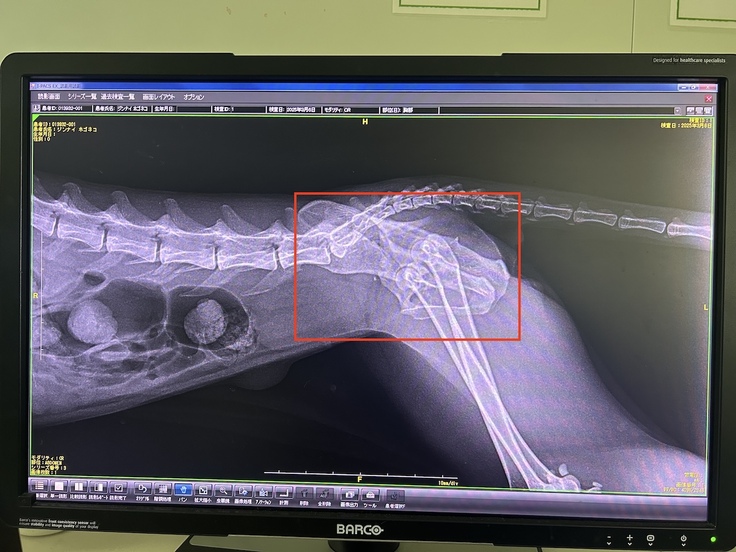

2025年3月13日(木)動物病院Aにて1回目(右側の骨盤骨折整復)の手術

先生から、手術前検査の結果について説明がありました。

術中に神経などを傷つけることなく,できるだけ安全に,そしてスムーズに手術を進めるために、レントゲンだけでなくCTも撮影しました。

その結果,両側の骨が内臓側から外へ向かって斜めに折れており,足の骨が内臓側に入り込んでいて,想像以上に深刻な状態でした。

手術は、大腸を圧迫していた右側の骨折から始まりました。

まず、ずれてしまった足の骨を元の位置に戻し、そこからプレートでしっかりと固定します。

手術は午後2時に始まり,終了したのは午後4時を過ぎた頃でした。

斜めに折れていたため,プレートを固定できるスペースが限られ,思った以上に時間がかかったそうです。

2025年3月17日(月)動物病院Aにて2回目(左側の骨盤骨折整復)の手術

1回目の手術から4日後,左側の骨折を治すための2回目の手術が行われました。

そして,手術は無事に終了したものの 「神経がしっかり機能するかどうか、今後も慎重に経過を見ていく必要があります」と先生に言われました。 ただ,朗報もありました。骨の状態から年齢もまだ1〜2歳程度と推定されるため、骨折した部分の回復は十分に期待できるということです。